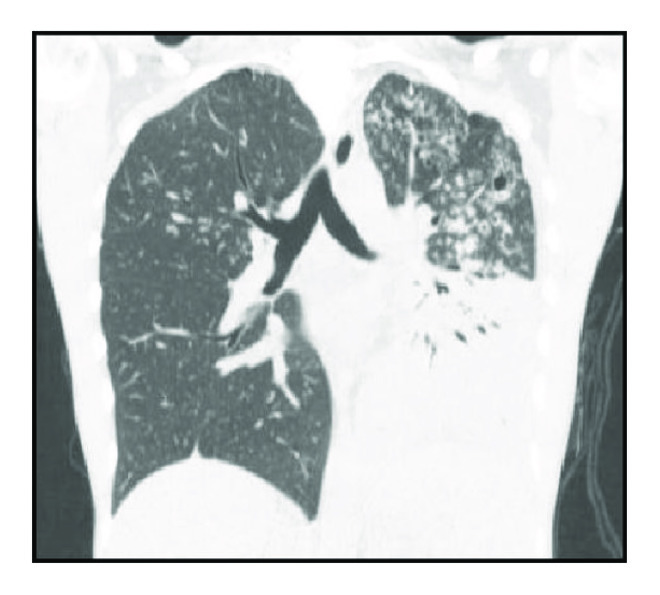

Regarding severity of the disease, multiple bilateral involvement was observed in 52 patients (70.3%) (Table 1 and Figure 1).

(a)

(b)

(c)

(d)

Tree-in-bud pattern was observed in 69 cases (93%) and was always associated with other types of injury, including consolidation in 57 cases (77%) and cavitary lesions in 46 cases (62%). Consolidations predominated in the upper lobes and occurred on the left lobe in 32 cases (56%) and on the right lobe in 22 cases (38%). Cavitary lesions predominated in upper lobes and occurred in upper left lobe in 22 cases (47.8%) and in upper right lobe in 15 cases (32.0%). The left and right lungs were affected separately in 12 cases (16.2%) and 10 cases (13.5%), respectively. Involvement of a single lobe was observed in 21% of cases, two lobes were involved in 21% of cases, three lobes in 19% of cases, and more than three lobes in 37% of cases. The upper lobe was affected in 72% of cases, the lingular and middle lobes were affected in 36% and 33% of cases, respectively, the right lower lobe was affected in 40% of cases, and the left lower lobe was affected in 60% of cases. Analysis by segment indicated that the most affected segments were the apical and posterior segments of the upper lobes in 63% and 66% of cases, respectively, and the apical segments of the lower lobes (41% of cases involving the right lobe and 52% of cases involving the left lobe).